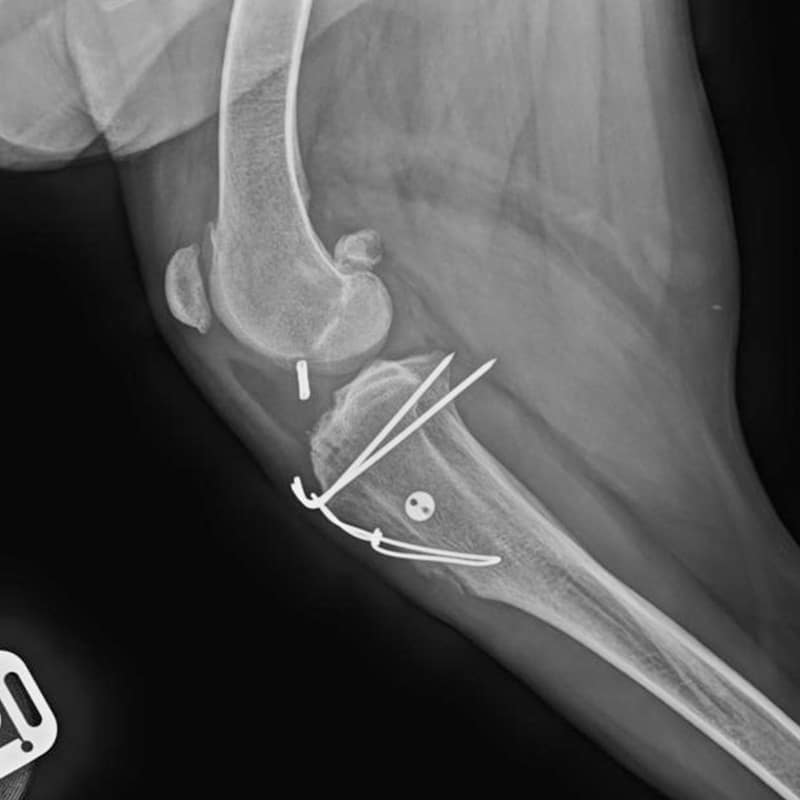

TPLOs

TPLOs and lateral suture for torn Cranial Cruciate ligaments in the knee.